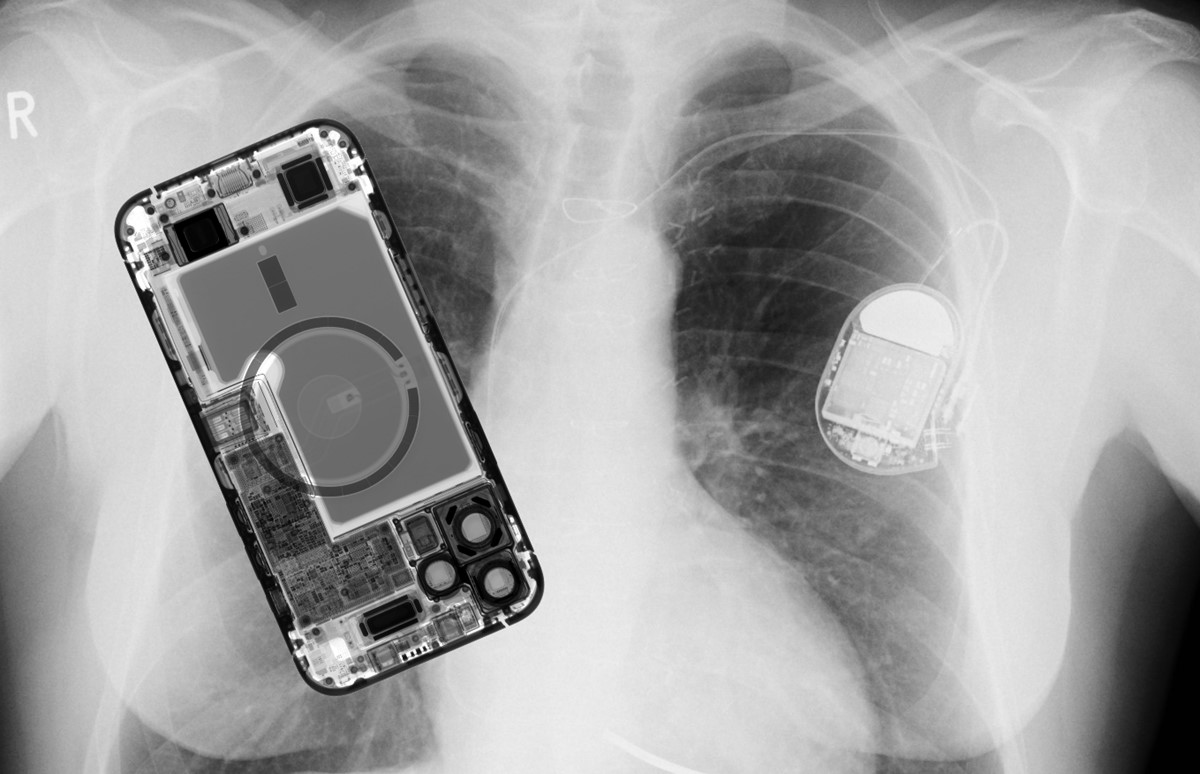

Apple potvrdio da je iPhone 12 potencijalna opasnost za pacemakere

Nedavno objavljeno istraživanje koje je pokazalo da magneti sustava MagSafe mogu poremetiti rad nekih uređaja za elektrostimulaciju srčanih mišića dobilo je i potvrdu od strane samog Applea

Nedavno smo pisali o tome kako su istraživači s američkog instituta Henry Ford Heart and Vascular Institute analizirali utjecaj magneta iz iPhonea 12 na uređaje za elektrostimulaciju srčanih mišića (popularnog naziva pacemakeri). Oni su utvrdili da su problemima u radu izloženi uređaji tipa imlantabilni kardioverter defibrilator (ICD) koji služe za automatsko zaustavljanje ventrikularne fibrilacije i tahikardije.

Ovi uređaji, zaključeno je, svojim vlasnicima mogu spasiti život, no ako im se iPhone 12 s MagSafe priključkom previše približi, moguće je da svojim magnetima aktivira magnetski prekidač i nakratko im omete normalan rad. Napomena o magnetima u novoj liniji iPhonea stajala je i tada na službenim stranicama Applea. U njoj je pisalo da "iPhone 12 sadrži više magneta nego prijašnji modeli, ali se ne očekuje da bi mogli predstavljati veći rizik magnetske interferencije s medicinskim uređajima od prethodnih modela iPhonea".

Apple je sada, vjerojatno potaknut ovim istraživanjem, nadopunio stranice svoje online korisničke podrške posebnim poglavljem koje se bavi samo pitanjem magneta unutar modela iPhone 12, iPhone 12 mini, iPhone 12 Pro, iPhone 12 Pro Max te njihovim MagSafe dodacima. Kako pišu iz Applea, svi ovi uređaji imaju magnete i primopredajnike elektromagnetskih signala.

Nove preporuke, koje do sada nisu bile istaknute, kažu da bi iPhone i njegove MagSafe dodatke trebalo držati najmanje 15 centimetara od svih medicinskih uređaja, odnosno najmanje 30 centimetara dok je u tijeku njihovo bežično indukcijsko punjenje. Apple preporuča svim korisnicima i da sa svojim liječnicima provjere karakteristike medicinskih uređaja koje koriste, kao i da pročitaju upute proizvođača i ravnaju se prema njima.